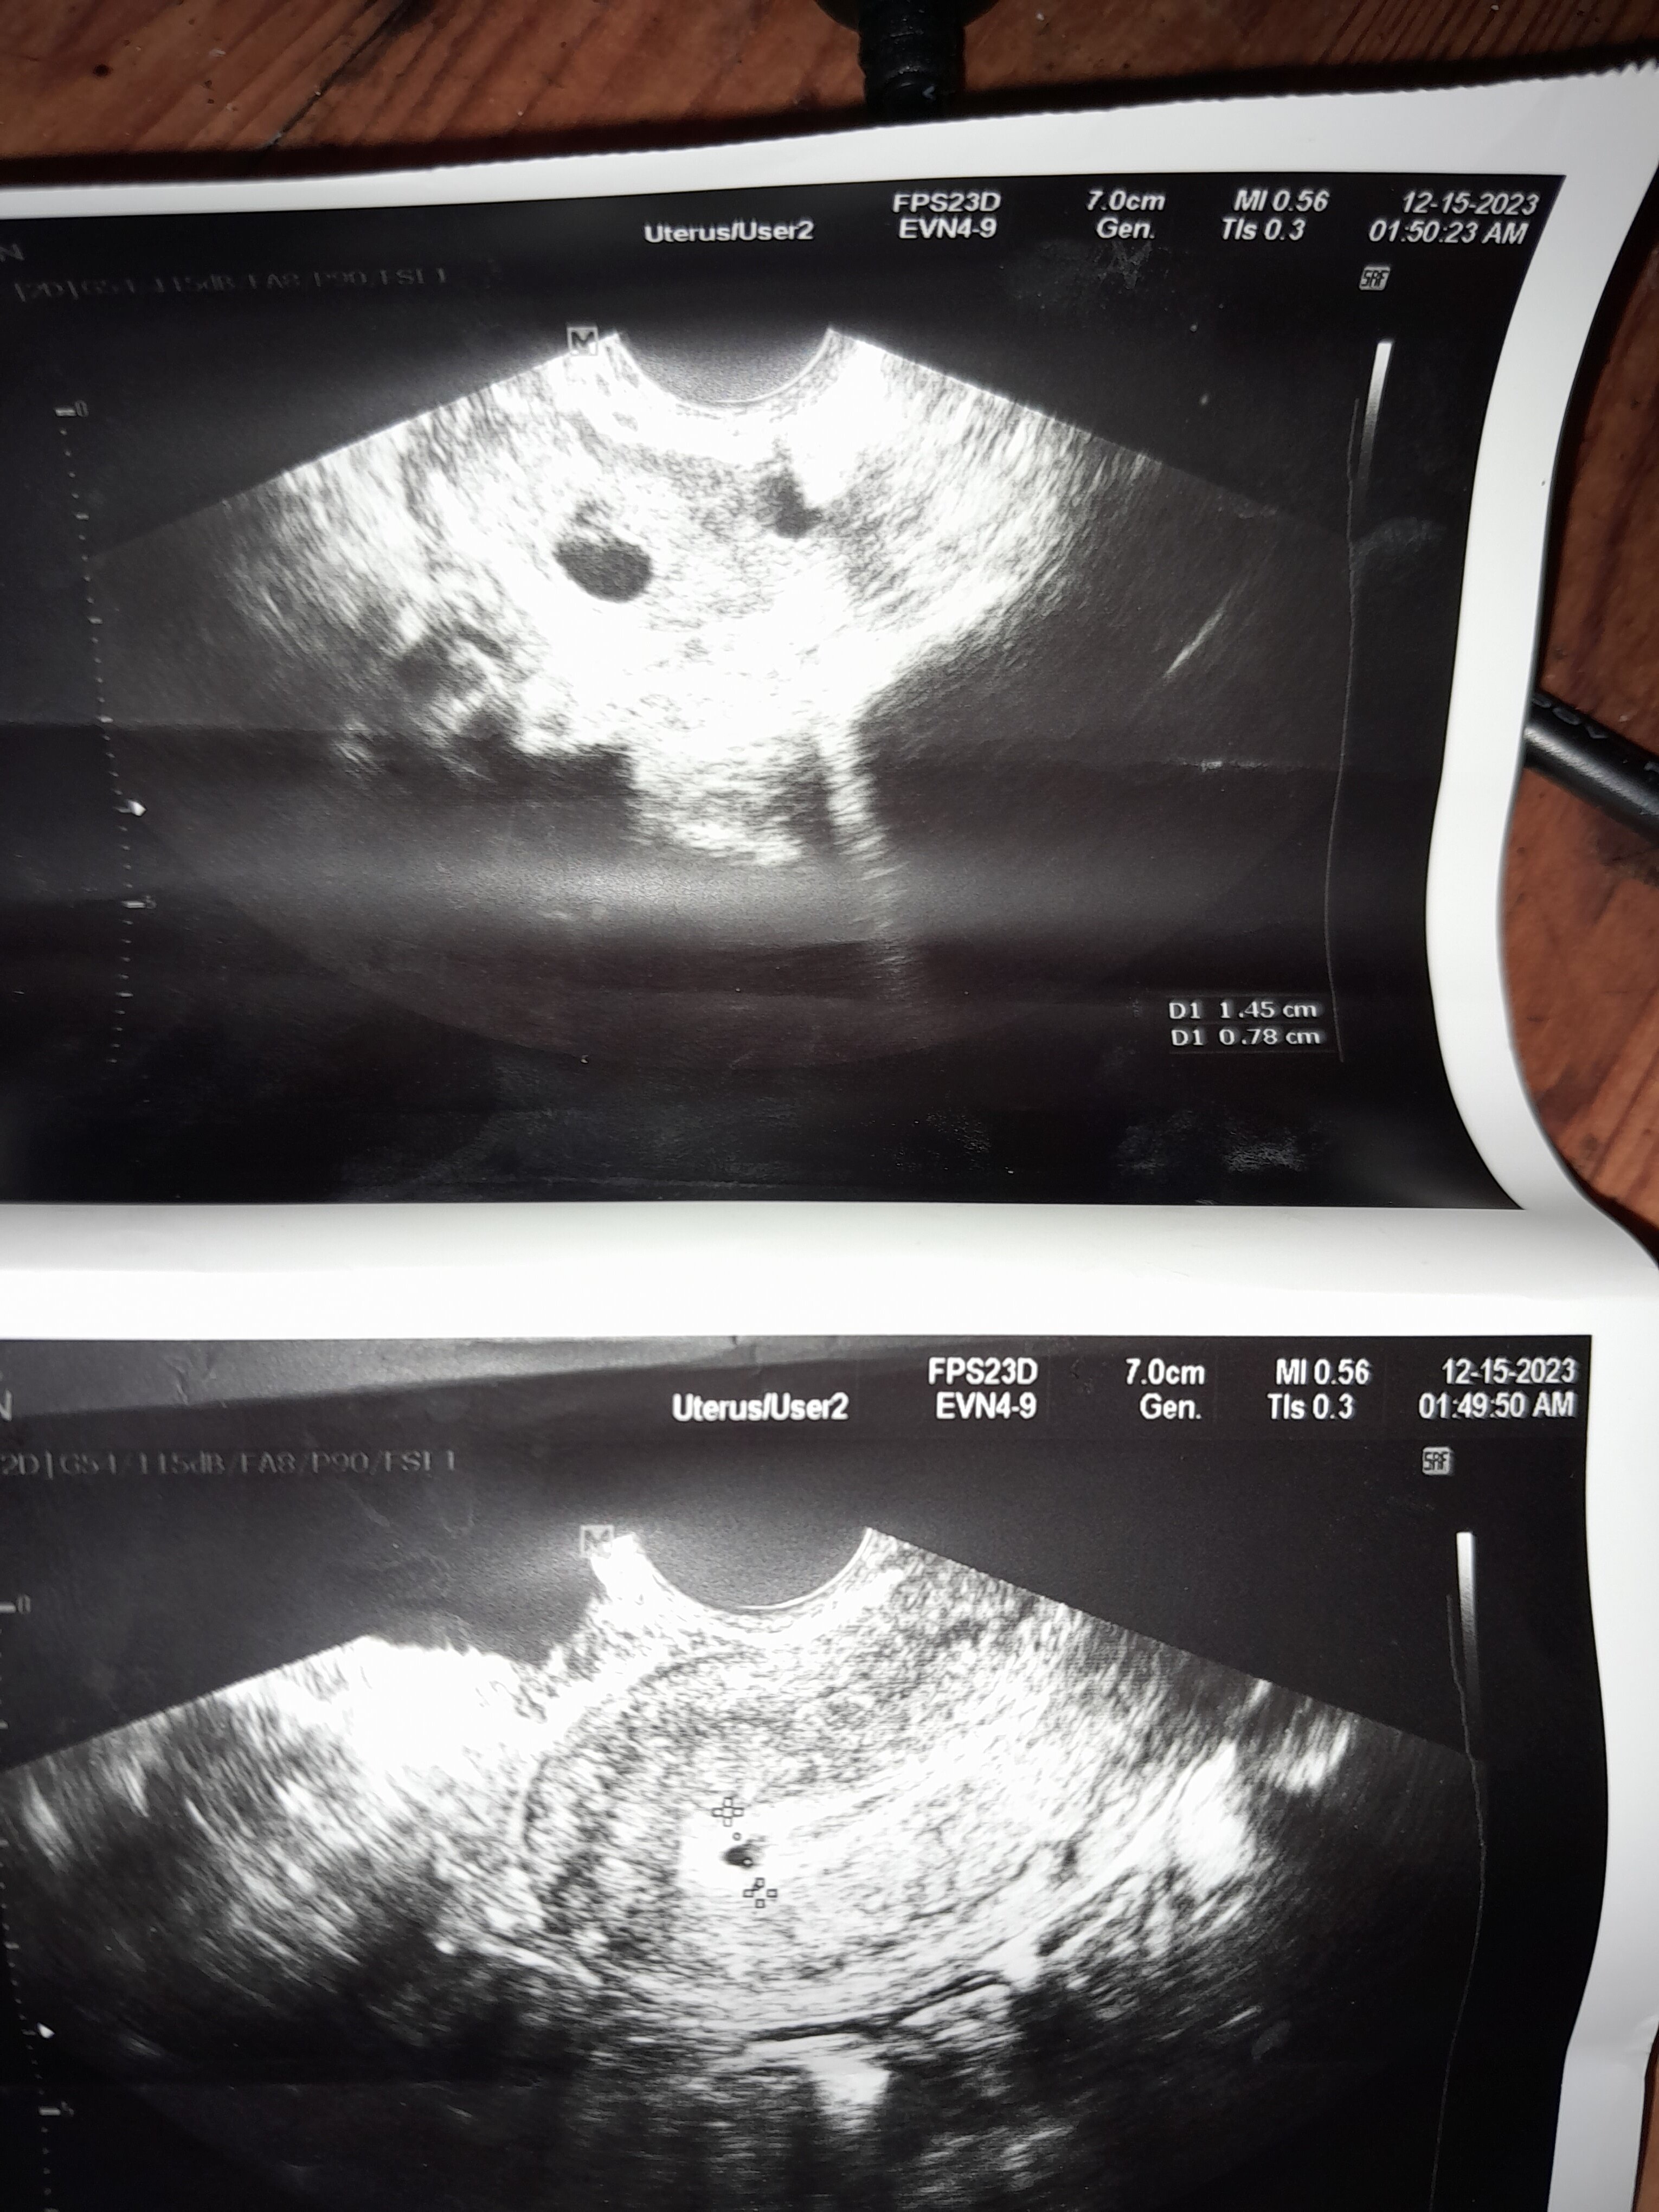

A co lekarz mówił skoro masz usg ?Mam nie regulslne miesisczki cov25 dni czy to ciaza 1.45cm